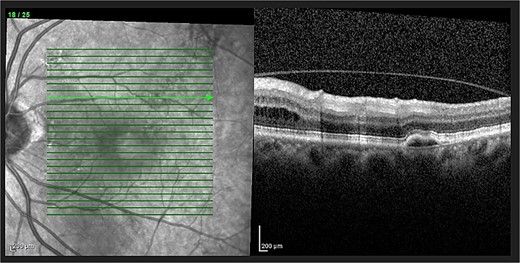

On examination, his corrected visual acuity on Snellen chart was 6/9.6-2 for his left eye and 6/60 for his right eye (baseline). Anterior segment examination was unremarkable. On dilated fundus exam, his right eye had longstanding macular atrophy. His left eye had a 0.3 pink disc, no swelling, with a blunted macular reflex. This can be seen in Fig. 1.

Optical coherence tomography (OCT) demonstrated an atrophied right macular. Whilst the left eye showed a thickened choroid, multiple pigment epithelial detachments (PED), subretinal fluid and intraretinal fluid nasally. This is shown in Figs 2 and 3.

(A) OCT of left eye – IRF and SRF with serous retinal detachment. Choroidal thickness = 454 μm.

The diagnosis of CSCR was made by the patient’s ophthalmologist, meeting diagnostic criteria as seen in Table 1. The patient meets major criteria with an OCT showing serous retinal detachment, and RPE alterations seen in Figs 2 and 3, respectively. Figure 2 displays a subfoveal choroidal thickness of 454 μm meeting the minor criteria.